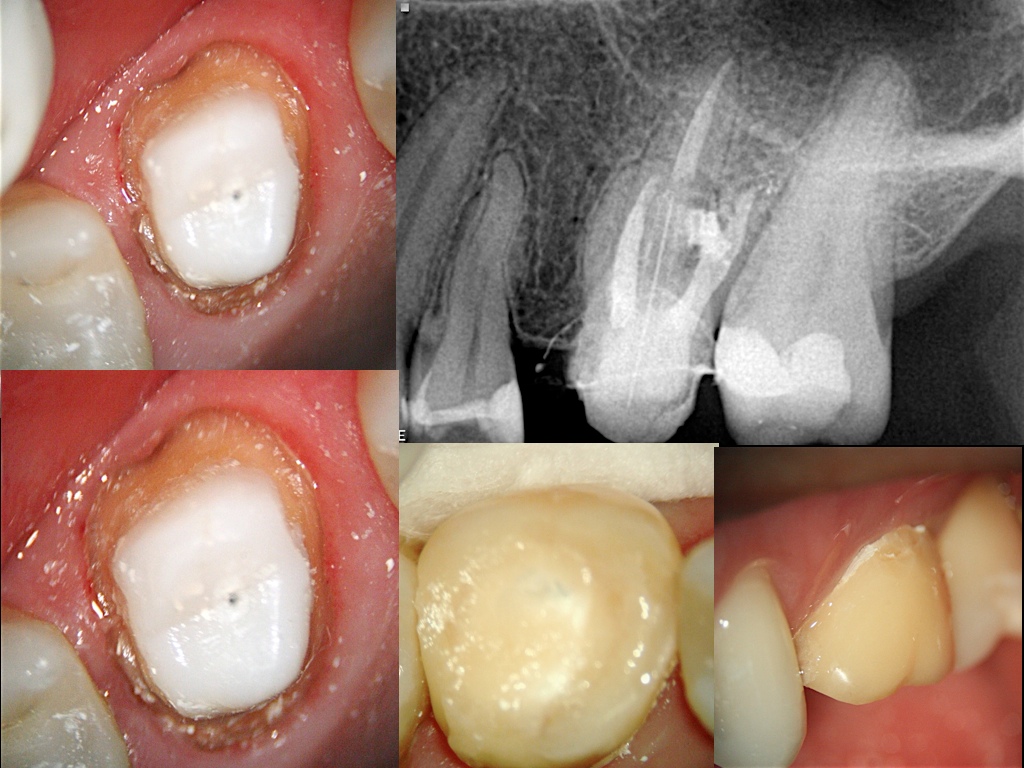

Retratamento Endodôntico - Prof. Flavia Casale Abe

Caso Clínico / Prof. Flavia Casale Abe

Retratmento e Reinstrumentação com limas Protaper Universal